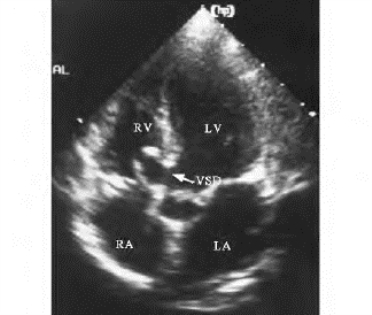

1.20.2二、室间隔缺损